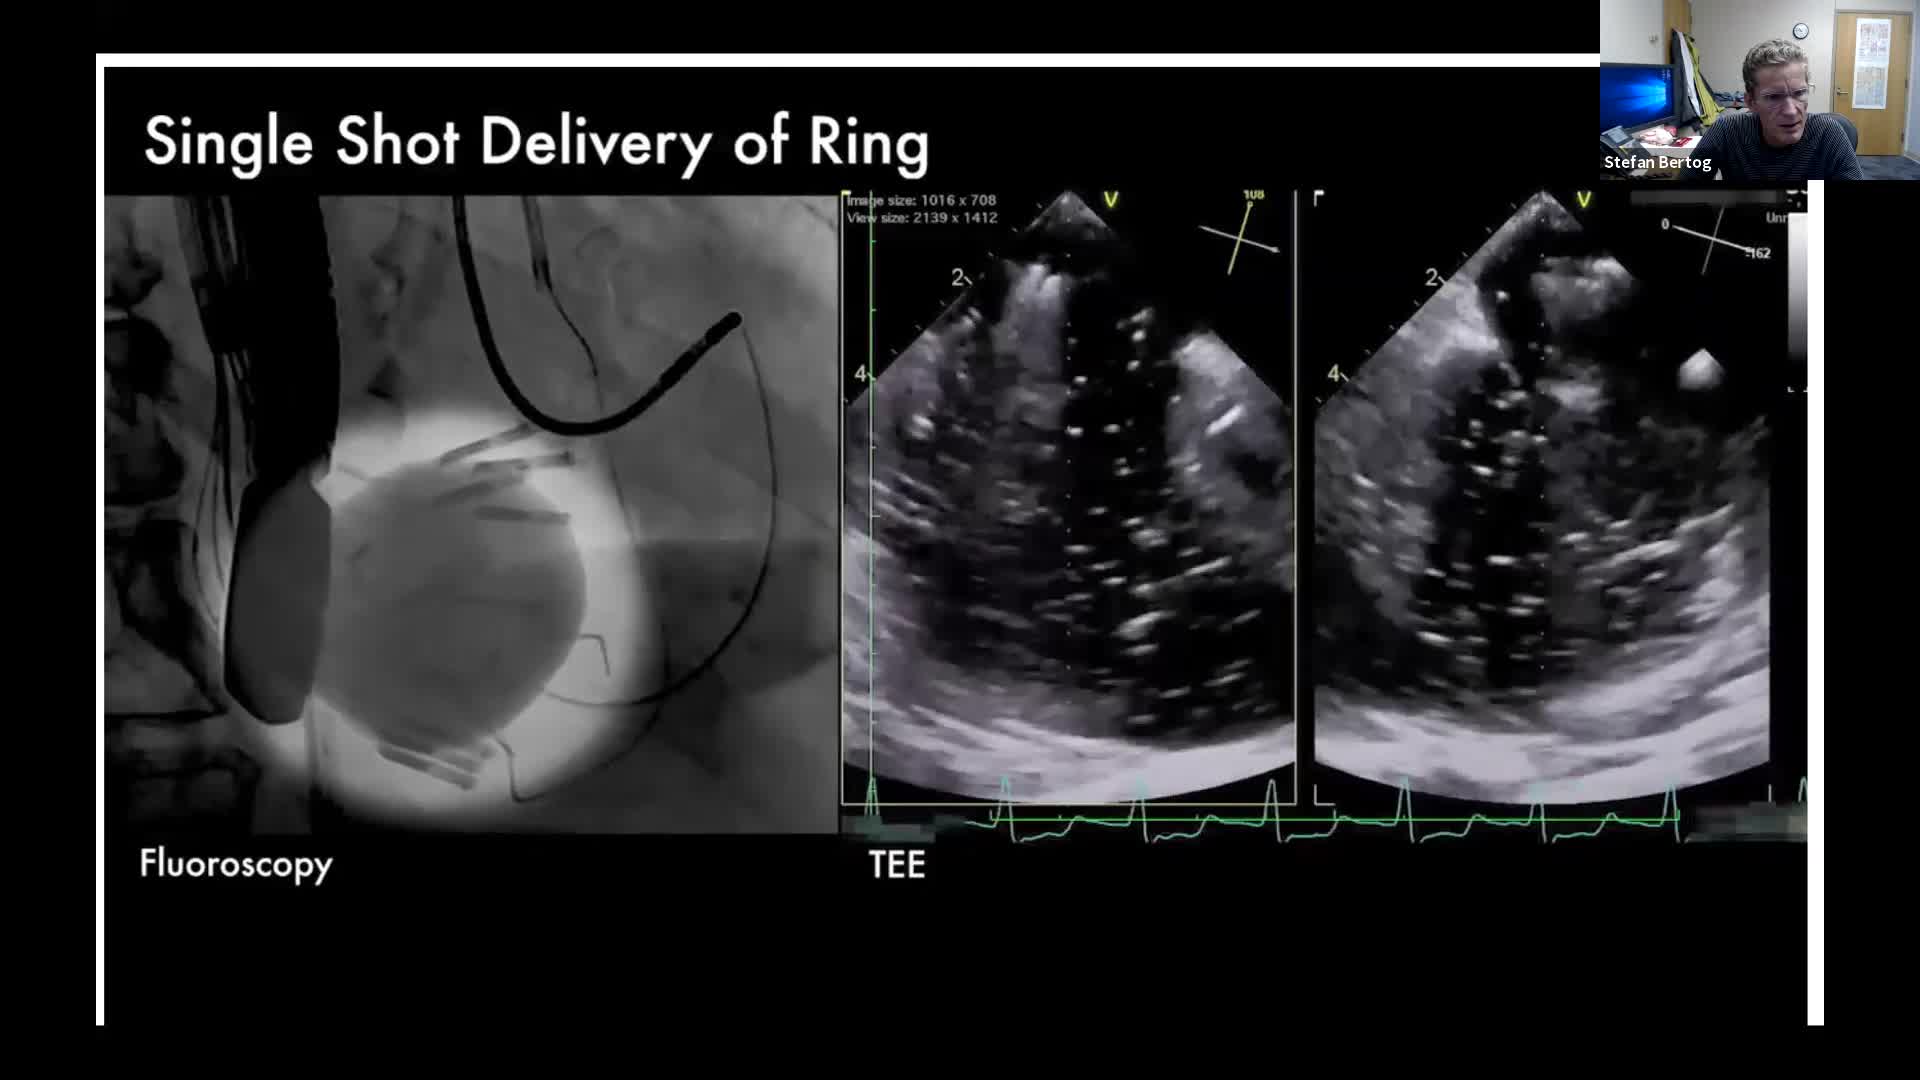

CSI CATHLAB LIVE - INTER-ATRIAL SHUNT FOR DECOMPRESSION OF THE LEFT ATRIUM IN A PATIENT WITH VERY SEVERE HEART FAILURE WITH THE AFR DEVICE